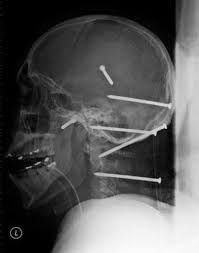

Kazayla Giren Nesneler

O Şişe Oraya Bakın Nasıl Girmiş…Röntgen filmlerinden çıkan akılalmaz şeyler Röntgen filmlerinden “akıl almaz şeyler Hastane koridorlarına düşenler bilir…